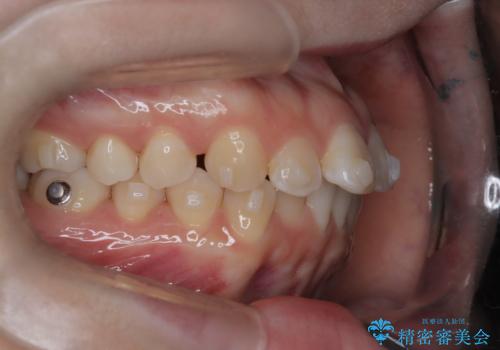

- 前歯のデコボコ(叢生)を気にされてご来院されました。精密な検査の結果、歯が並ぶスペースが不足していることが判明。患者様のご希望から、透明で目立ちにくいインビザライン(マウスピース矯正)による治療計画を立案しました。抜歯を避け、奥歯全体を奥へ動かす遠心移動という方法でスペースを確保し、前歯の叢生を解消することを目指します。

今回の矯正治療では、透明なマウスピース型の装置インビザラインを使用しました。この装置は取り外し可能で、日常生活で目立ちません。治療は、緻密に計算された計画に基づき、段階的に作製されたマウスピースを交換していくことで、奥歯から順に全体を後方へ移動させる遠心移動を実施。これにより、前歯を並べるための十分なスペースが確保され、デコボコが解消されました。抜歯することなく、機能的にも審美的にも整った美しい歯並びを獲得していただけました。